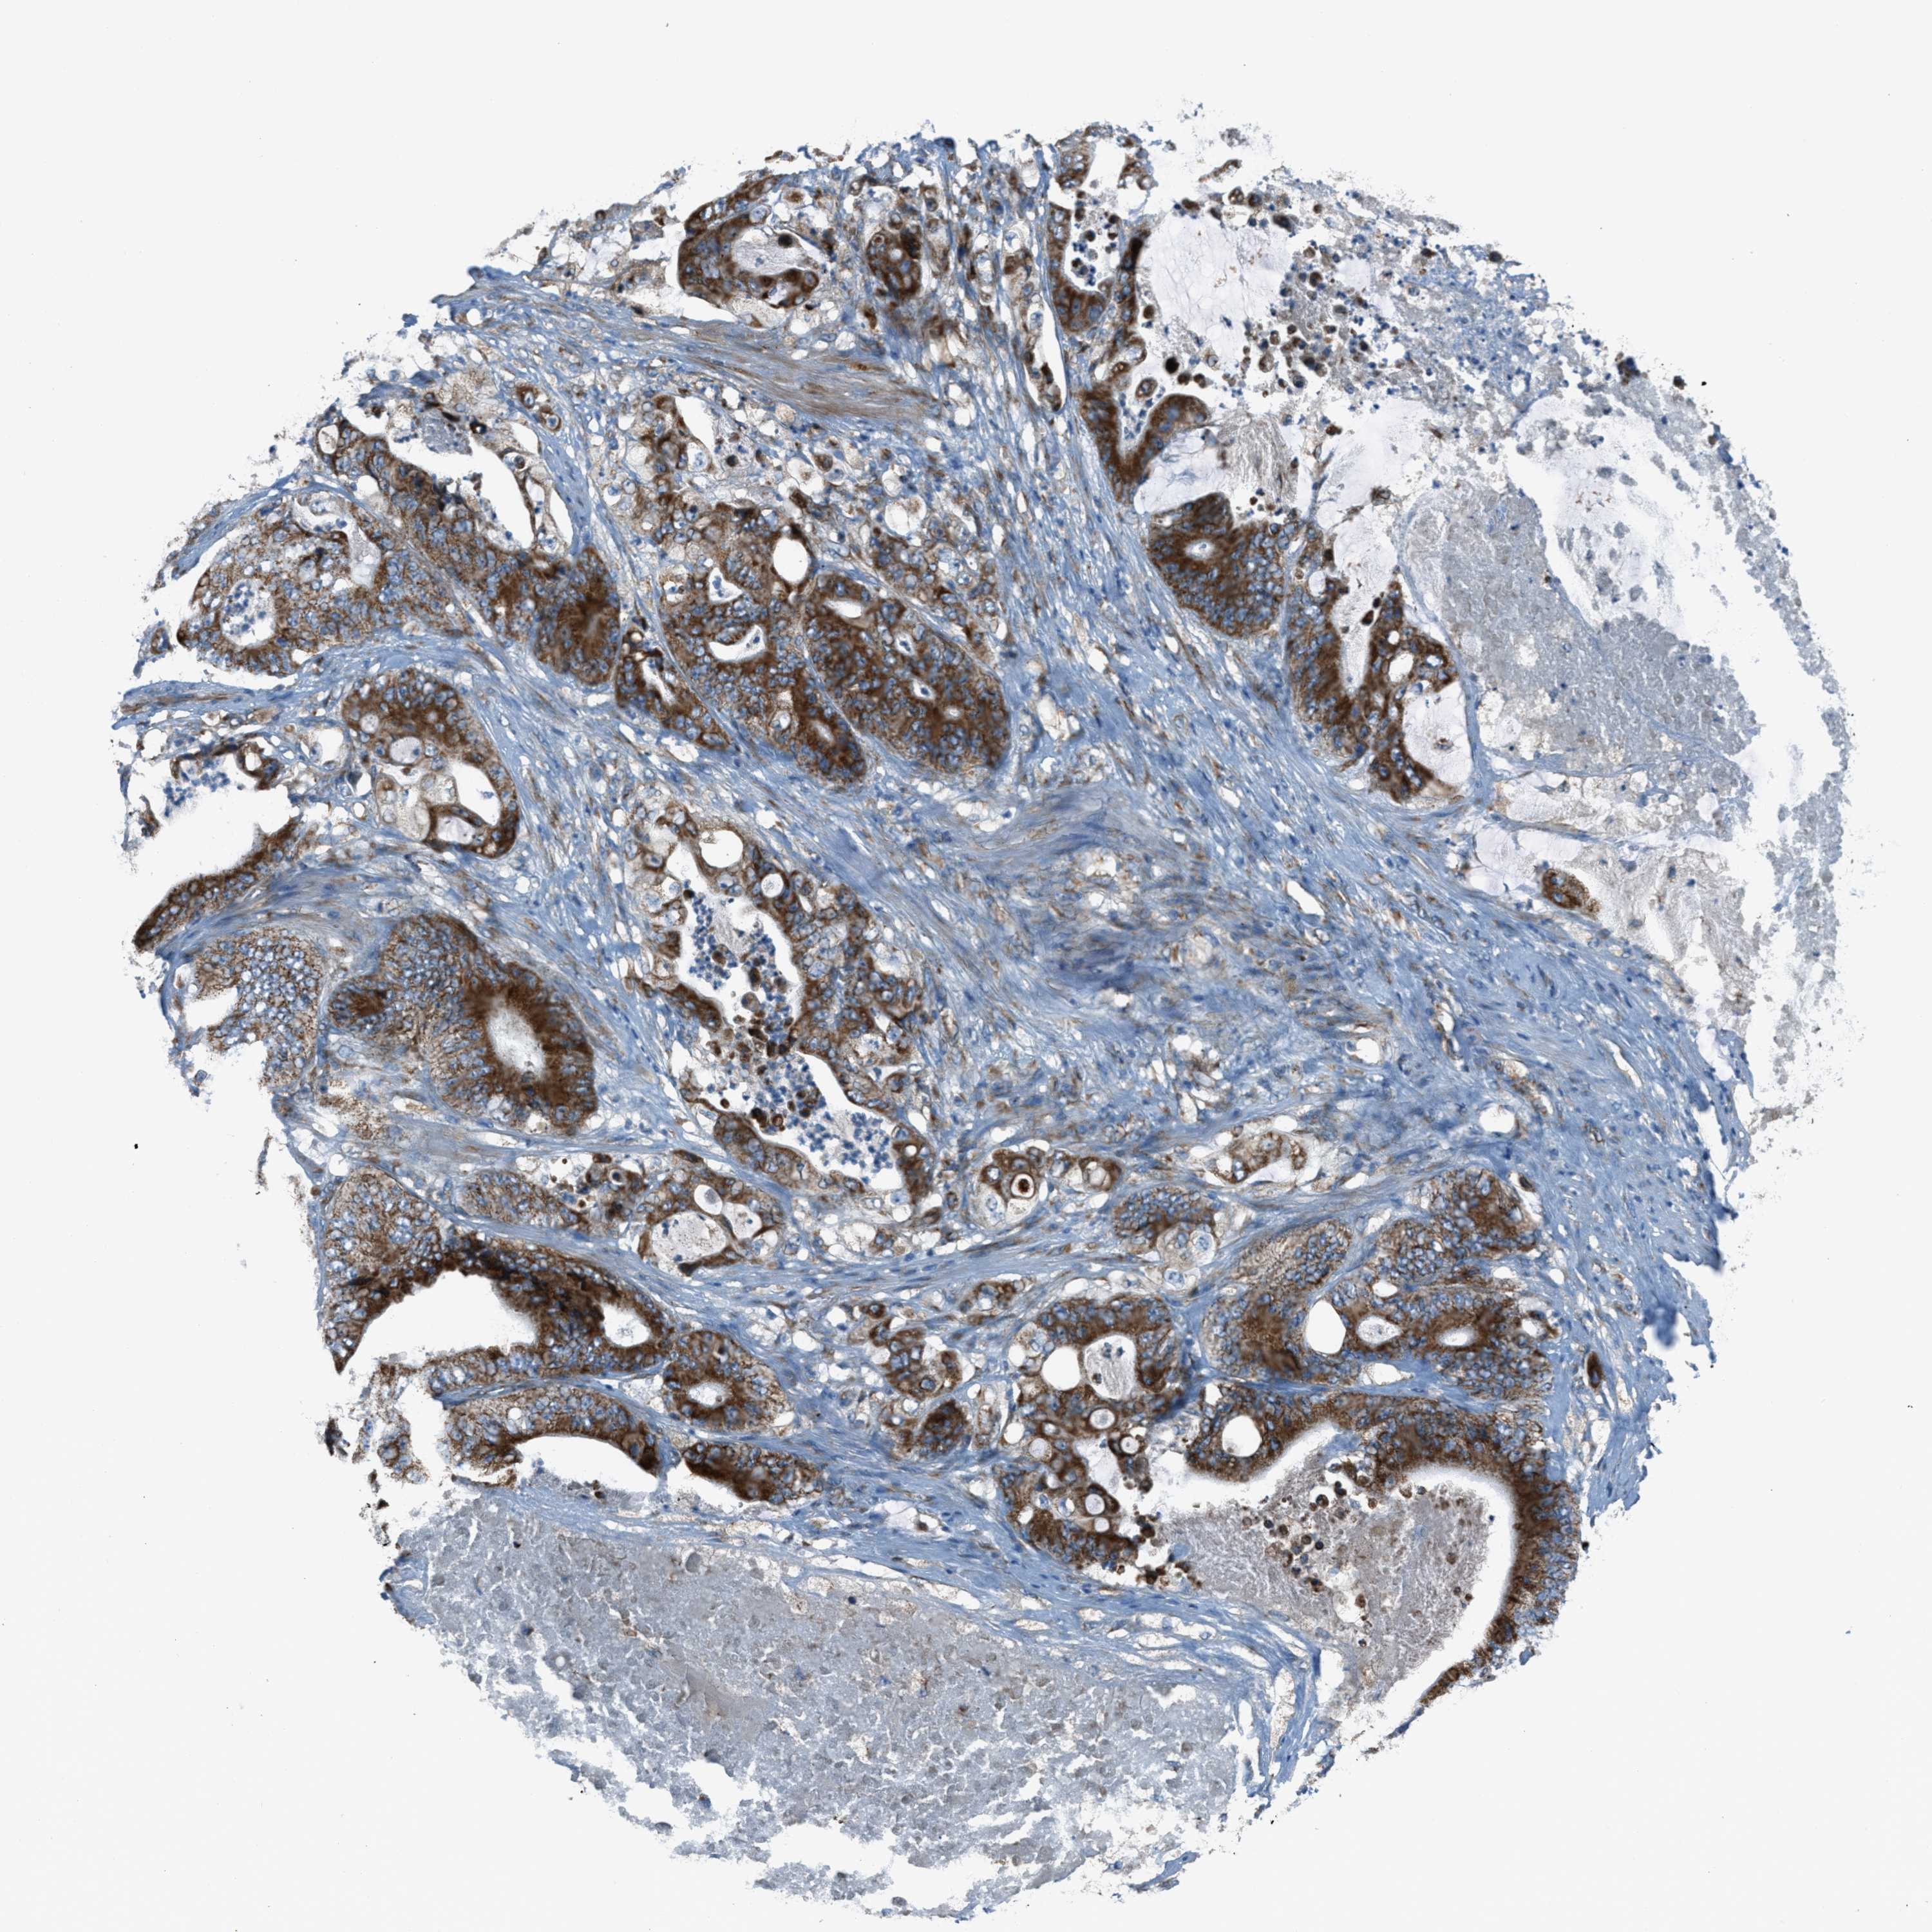

STOMACH CANCER - Protein expressioni

A mouse-over function shows sample information and annotation data. Click on an image to view it in a full screen mode. Samples can be filtered based on level of antibody staining by selecting one or several of the following categories: high, medium, low and not detected. The assay and annotation is described here.

Antibody stainingi

Antibody staining in the annotated cell types in the current human tissue is reported as not detected, low, medium, or high, based on conventional immunohistochemistry profiling in selected tissues. This score is based on the combination of the staining intensity and fraction of stained cells.

Each image is clickable and will lead to virtual microscopy that enables deeper exploration of all samples and also displays staining intensity scores, fraction scores and subcellular localization as well as patient and tissue information for each sample.

Antibody HPA017995

Staining

High

Medium

Low

Not detected

Intensity

Strong

Moderate

Weak

Negative

Quantity

>75%

75%-25%

<25%

None

Location

Nuclear

Cytoplasmic/membranous

Cytoplasmic/membranous,nuclear

Adenocarcinoma, NOS